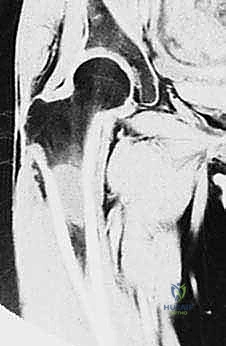

| الرنين المغناطيسي (MRI) | (المعيار الذهبي) يوفر صوراً فائقة الدقة للأنسجة الرخوة، العضلات، الأعصاب، الأوعية الدموية، وامتداد الورم داخل نخاع العظم. | أساسي لتحديد "الهوامش الجراحية الآمنة" ومعرفة ما إذا كان الورم قد مس الأعصاب أو الأوعية. |

- تحديد الهوامش الجراحية (Surgical Margins): بناءً على صور الرنين المغناطيسي، يحدد الدكتور هطيف بالضبط أين سيقطع العظم. الهدف هو إزالة الورم مع غلاف من الأنسجة السليمة المحيطة به (هامش واسع) لضمان عدم ترك أي خلية مريضة.